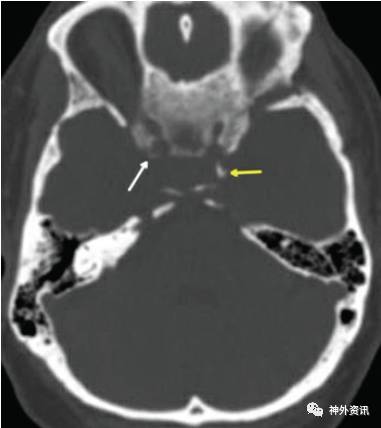

图5. 薄层CT(骨窗)显示一不完全性颈内动脉床突孔(白色箭头)和一完全性床突间骨桥(黄色箭头),该例患者为蝶骨嵴内侧型脑膜瘤。